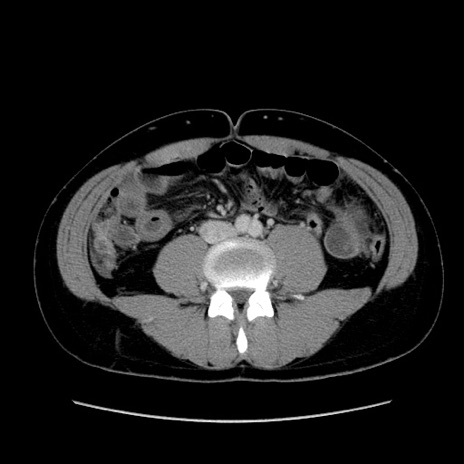

症例36(横断像)

【症例】20歳代 男性

【主訴】心窩部痛

【現病歴】今朝より上腹部痛あり。一旦軽快していたが再度出現したため救急要請。昨日夕に白身の魚を含む刺身を食べた。

【身体所見】BP 136/89mmHg、HR 74/min、BT 37.0℃、腹部:膨満、軟、心窩部に圧痛あり。反跳痛なし、筋性防御なし、腸雑音やや亢進あり。

【データ】WBC 17700、CRP 0.48